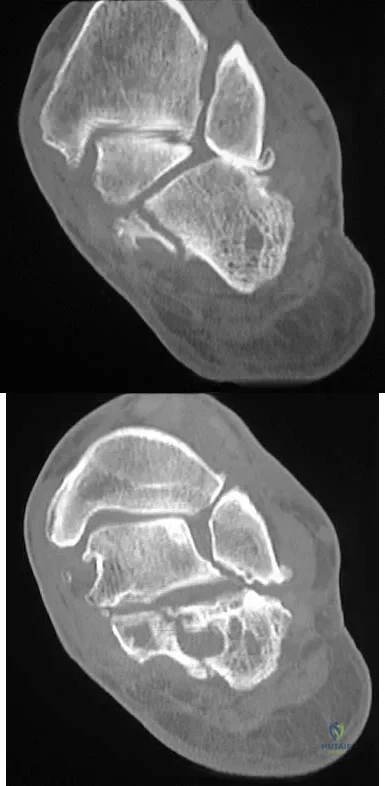

A 50-year-old laborer sustained an isolated closed injury to his heel after falling 11 feet off a wall. A radiograph and a CT scan are shown in Figures 4a and 4b. To minimize the patient's temporary disability and allow him to return to work most rapidly, management should consist of

Explanation